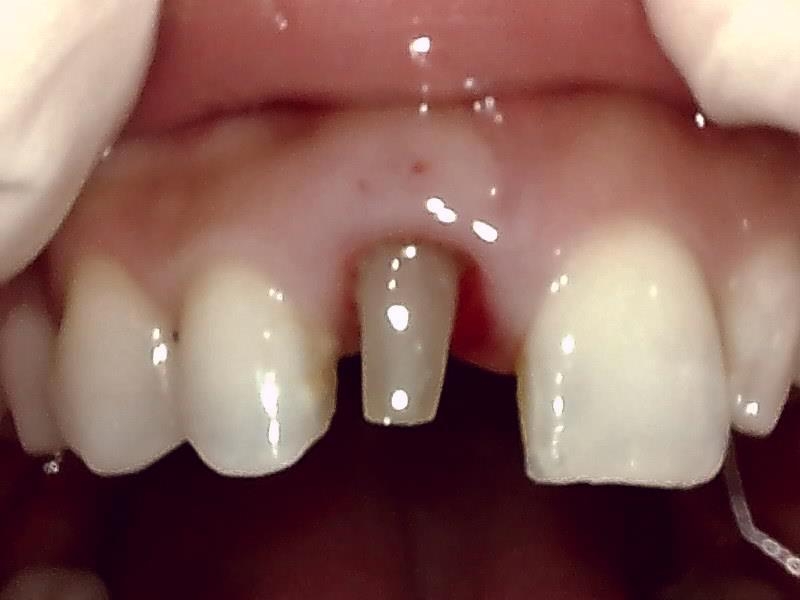

ジルコニアセラミック冠の装着前の支台歯形成(写真)

写真; ジルコニアセラミック冠装着前の歯冠形成